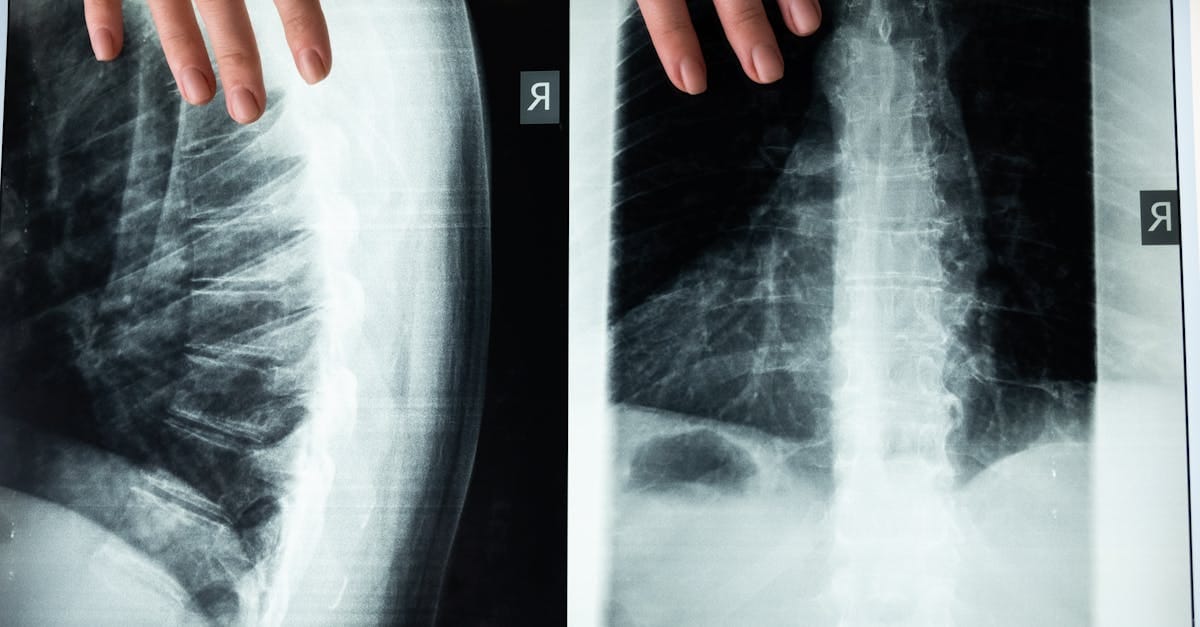

- Diagnosis: Medical imaging (MRI, X-rays).

Spinal stenosis is a condition characterized by the narrowing of the spinal canal, the space that houses the spinal cord and nerve roots. This narrowing can lead to pressure on the nerve structures, causing varied symptoms such as pain, numbness, or difficulties walking. Spinal stenosis is often caused by degenerative factors, including arthritis, and primarily affects older individuals. As the spine ages, modifications to its structures can occur, leading to a decrease in the caliber of the spinal canal.

Spinal stenosis is a common condition that primarily results from the narrowing of the spinal canal, causing pressure on the spinal cord and spinal nerves. This compression can lead to various symptoms, including pain, numbness, and difficulties walking. Effective treatments, such as spinal decompression, are essential to relieve the signs and improve the quality of life of patients suffering from this pathology.

Quels examens sont nécessaires avant de commencer un traitement de décompression?

Un examen clinique approfondi et des imageries comme une IRM ou une radiographie sont souvent nécessaires.